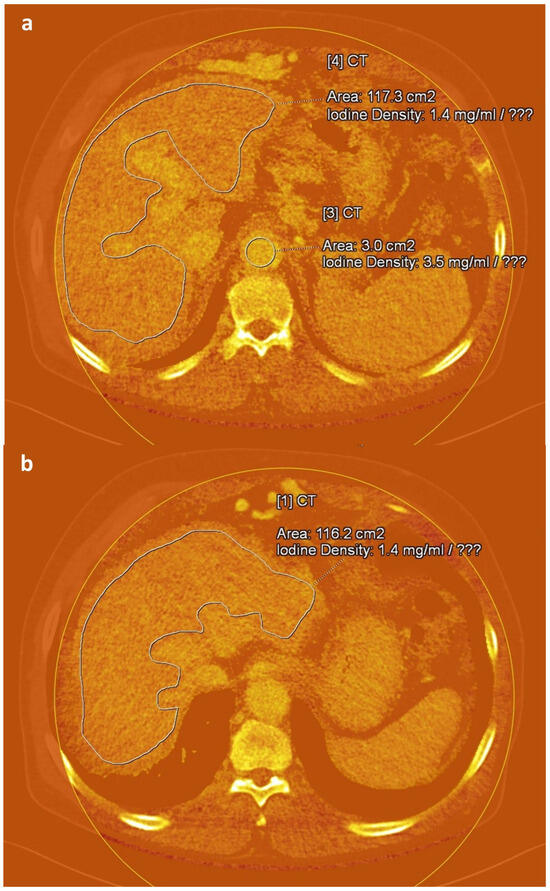

Figure 2. Axial iodine maps generated from equilibrium-phase images obtained 3 min after contrast administration at 100/140 Sn kVp in a 72-year-old man with alcohol-induced liver cirrhosis. Freehand (a,b) and circular (a) regions of interest are delineated in the liver and aorta, respectively, at different anatomical levels on the iodine maps.

An abdominal radiologist (J.E.K., 17 years of experience in CT interpretation), blinded to all clinical information, manually delineated regions of interest (ROIs) on iodine maps reconstructed from equilibrium-phase images using the Liver VNC tool provided in the syngo.via software platform (version VB60S; Siemens Healthineers, Erlangen, Germany). For each case, three free-hand ROIs were placed along the margin of the liver at the anatomical levels of the intrahepatic inferior vena cava confluence, portal vein hilum, and gallbladder fossa, while carefully avoiding major vessels and focal hepatic lesions. To reduce variability due to scan timing, three circular ROIs were additionally positioned in the aorta at the origins of the celiac trunk, superior mesenteric artery, and renal arteries [31] (Figure 2). The average iodine concentration values derived from these ROIs were used to represent hepatic iodine content (IC_Liver) and aortic iodine content (IC_Aorta). Based on these values, fECV score was computed using the following formula [18,19,31]: